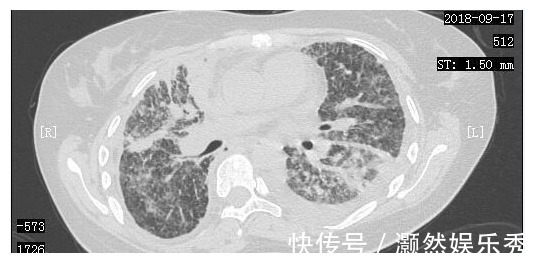

在经历了短暂的绝望后,小周一家决定齐心协力,积极进行抗癌治疗。2018年9月7日,小周进行了胸腔穿刺抽液,同时进行了胸腔灌注化疗。2018年9月14日,小周来到了我们医院进行治疗,复查了胸部CT,当时的胸部CT显示肺部一般情况非常差。